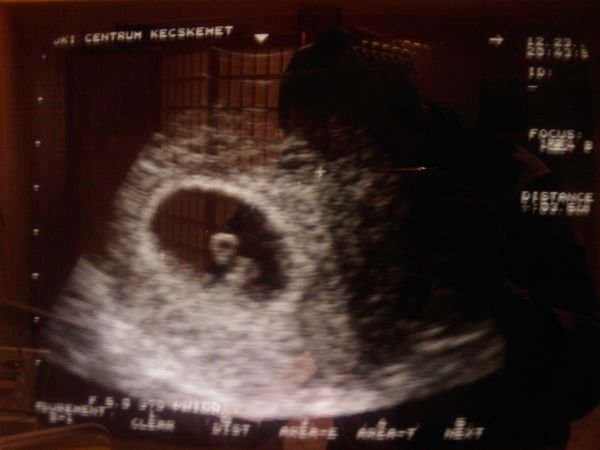

Feltétlen üzenj, ha kiderült, hogy újabb punis lapul a pocakban, mert sztem az!